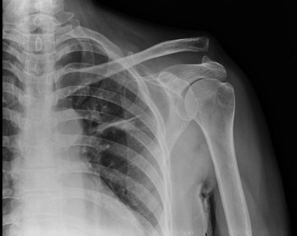

Acromioclavicular joint subluxation and dislocation account for approximately 10% of all traumatic shoulder injuries. (1; 3) AC joint injury results from either direct or indirect injury to the shoulder. Direct injury to the joint occurs with a direct blow to the shoulder or, more commonly, when an individual falls with their arm in an adducted position. Indirect injury to the AC joint typically occurs as a result of a fall on an outstretched hand. (1; 4) On exam, patients will have pain over the acromioclavicular joint and pain with range of motion of the shoulder. (3) Patients may hold their arm in an adducted position and there may be a visible or palpable step-off deformity over the AC joint. Additionally, the ipsilateral clavicle may appear to be high-riding or the ipsilateral shoulder may appear displaced inferiorly (Figure 5). (1; 3) In less obvious cases, provocative maneuvers (such as the cross-body adduction test and AC shear test) may be used to localize discomfort to the AC joint. (2)

Figure 5

Figure 5: Greene, Tim (ND). CoreEM: Acromioclavicular joint injury. Obtained from <https://coreem.net/core/ac-joint-injuries/>.